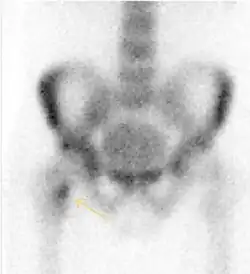

Nuclear Medicine

Bone scanning in people with hip pain can be complementary to other imaging studies, mainly in indeterminate bone lesions to clarify whether it is an active lesion with abnormal radiotracer accumulation. Nevertheless, MRI has replaced scintigraphy in the diagnosis of most of these conditions. An example is stress or insufficiency fractures: increased uptake is usually present in around 80% of fractures within 24 h, and 95% of fractures reveal activity by 72 h following trauma, showing an overall sensitivity of 93% and specificity of 95%. MRI is superior to bone scans in terms of sensitivity (99%-100%) and specificity (100%). Moreover, a bone scan does not provide detailed anatomical location of the fracture, and further imaging is usually required.[1]